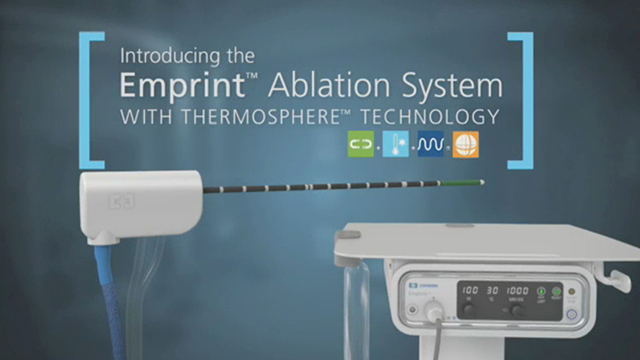

2. Διαδερμική Ψυχόμενη Αντένα προκαθορισμένης σφαιρικής θερμικής κατάλυσης (MWA)

2. Διαδερμική Ψυχόμενη Αντένα προκαθορισμένης σφαιρικής θερμικής κατάλυσης (MWA)